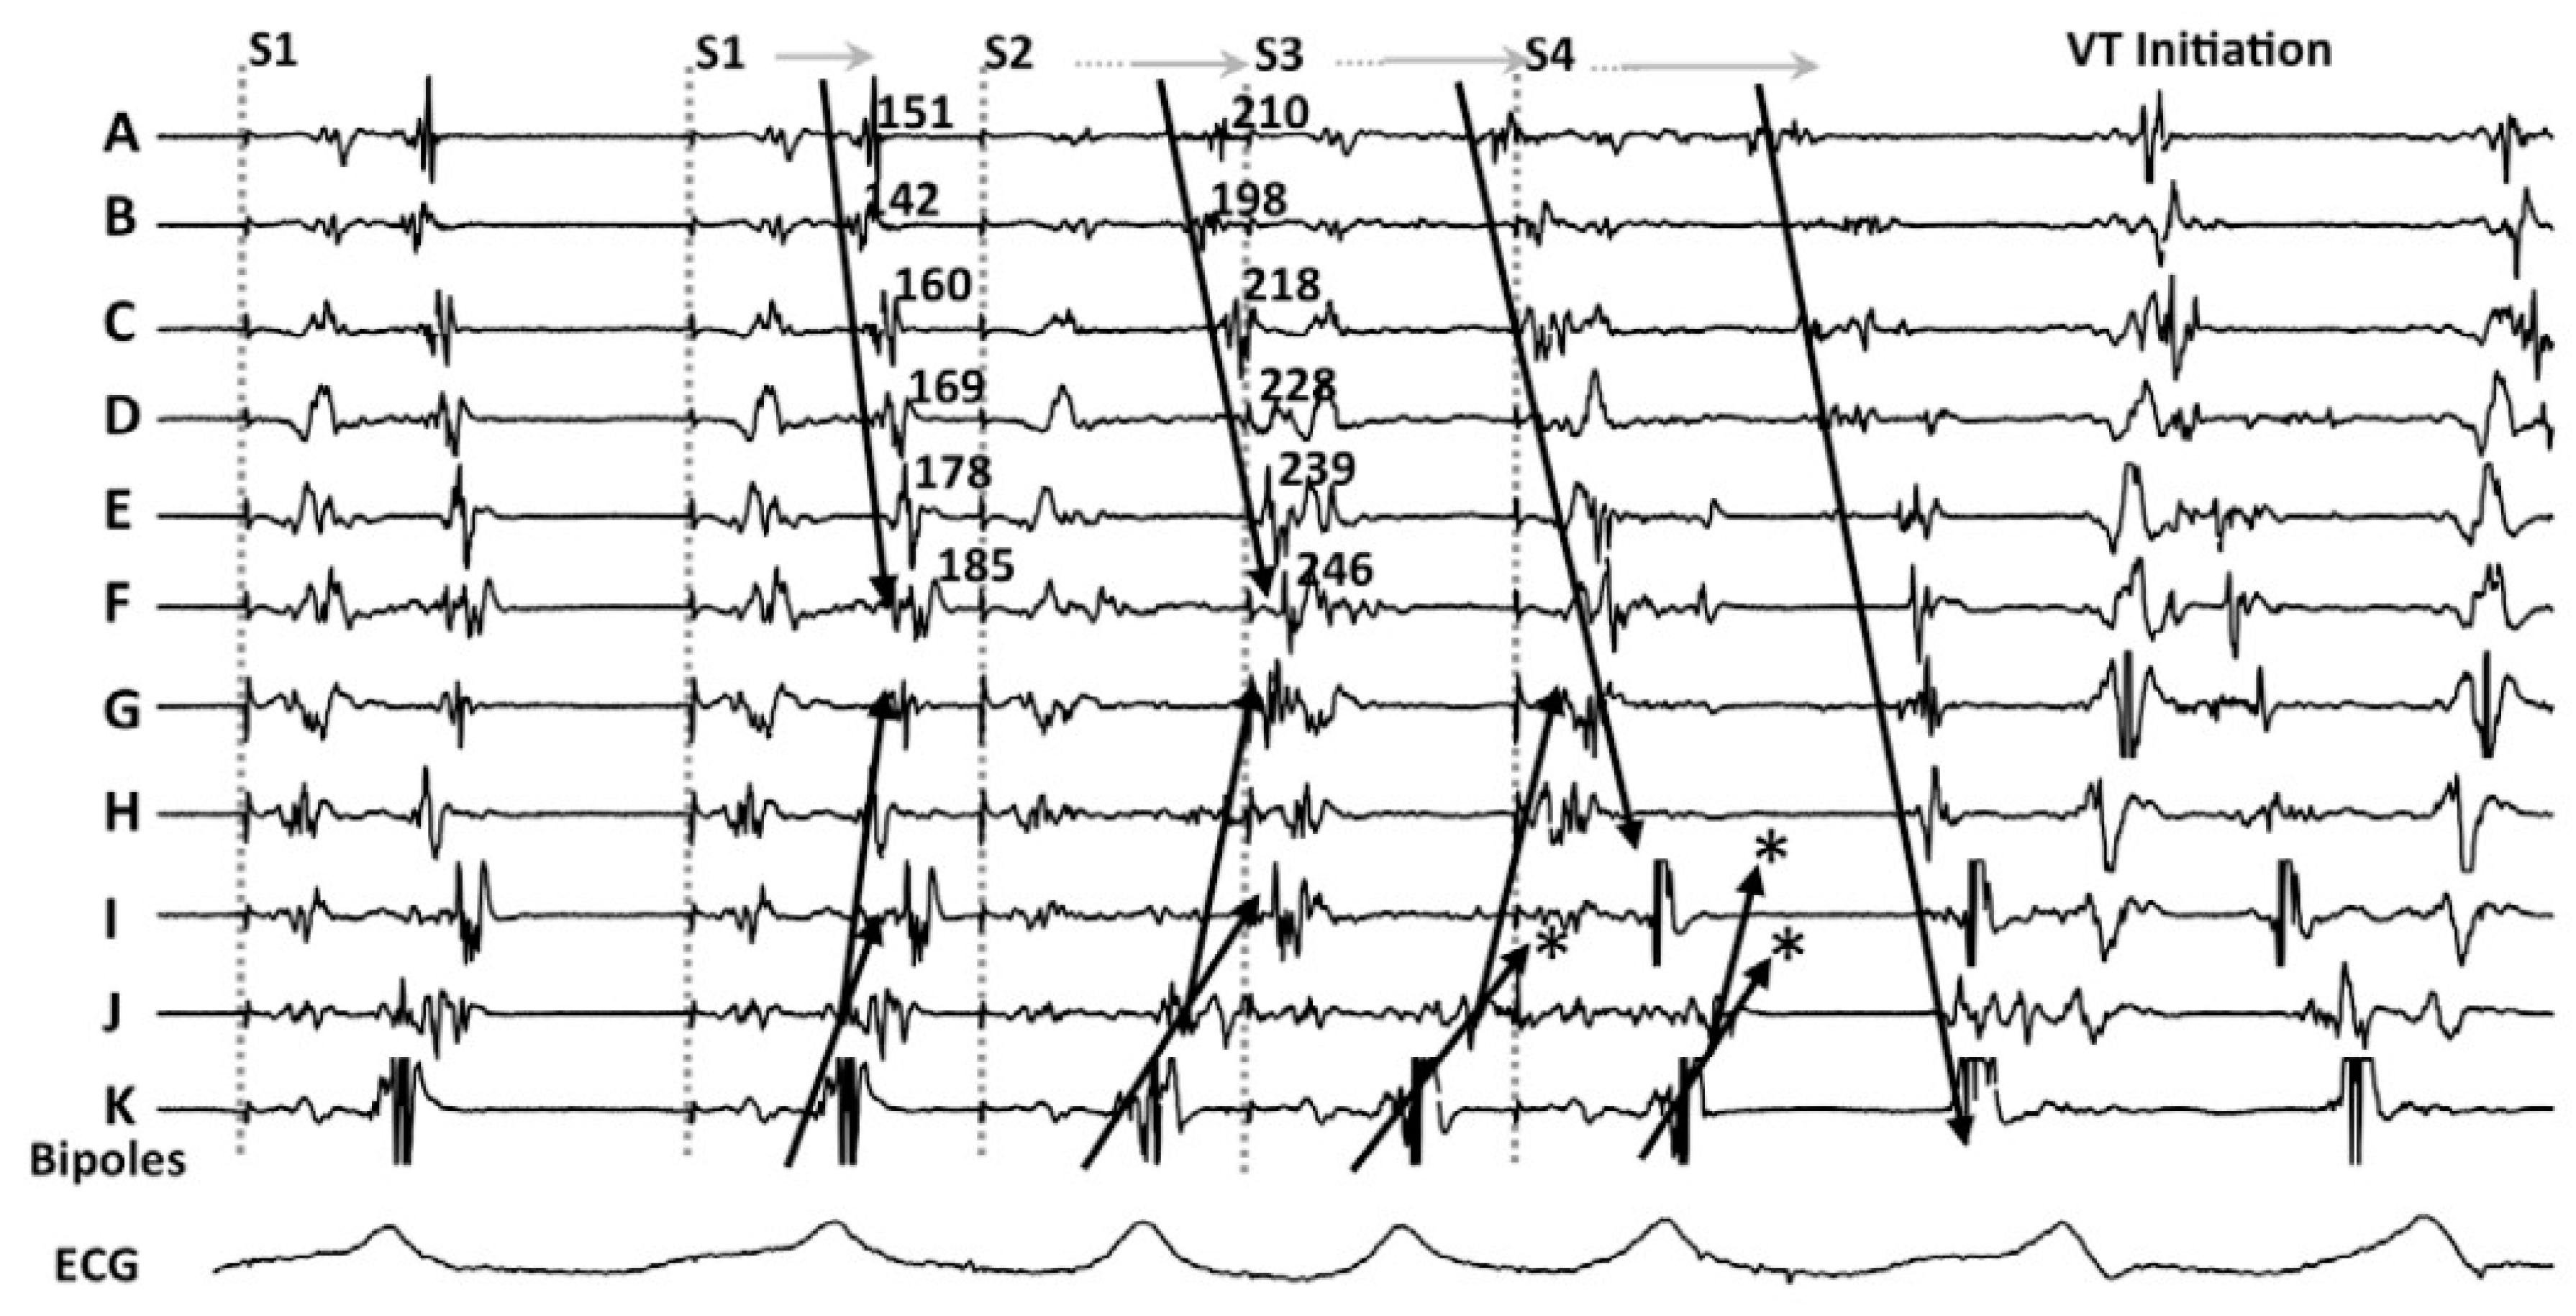

3.1. Decrement Evoked Potential (DEEP) Mapping

- Jackson, N.; Gizurarson, S.; Viswanathan, K.; King, B.; Massé, S.; Kusha, M.; Porta-Sanchez, A.; Jacob, J.R.; Khan, F.; Das, M.; et al. Decrement Evoked Potential Mapping: Basis of a Mechanistic Strategy for Ventricular Tachycardia Ablation. Circ. Arrhythmia Electrophysiol. 2015, 8, 1433–1442. [Google Scholar] [CrossRef]

- Porta-Sanchez, A.; Jackson, N.; Lukac, P.; Kristiansen, S.B.; Nielsen, J.M.; Gizurarson, S.; Massé, S.; Labos, C.; Viswanathan, K.; King, B.; et al. Multicenter Study of Ischemic Ventricular Tachycardia Ablation with Decrement-Evoked Potential (DEEP) Mapping with Extra Stimulus. JACC Clin. Electrophysiol. 2018, 4, 307–315. [Google Scholar] [CrossRef]